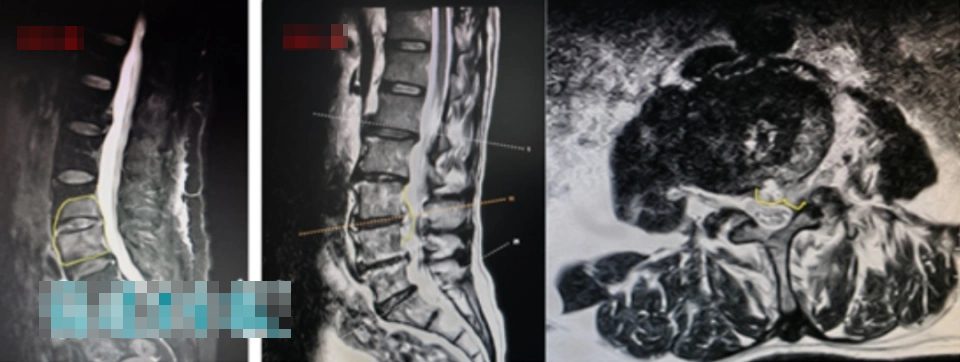

Vài ngày sau, kết quả xét nghiệm đã có - cả hai vợ chồng đều “dương tính với kháng thể brucellosis”; chụp cộng hưởng từ (MRI) cũng cho thấy có dấu hiệu viêm rõ ràng ở các khoảng gian đốt sống và các đốt sống liền kề của cột sống thắt lưng.

Trong đó, tình trạng của chồng bà Trương nghiêm trọng hơn: cột sống thắt lưng của ông không chỉ bị nhiễm trùng mủ mà tình trạng viêm nhiễm còn lan vào ống sống, khiến cột sống thắt lưng của ông trở nên vô cùng không ổn định. Ông có nguy cơ gặp phải những hậu quả nghiêm trọng như tê liệt và đau nhức ở chân, yếu cơ, thậm chí là liệt toàn thân và tiểu không tự chủ bất cứ lúc nào.

"Vì xương và đĩa đệm cột sống thắt lưng đã bị vi khuẩn 'ăn mòn', và ổ áp xe đã xâm lấn vào ống sống, nên trước tiên chúng tôi cần loại bỏ các tổn thương nhiễm trùng cho cặp vợ chồng này, sau đó cấy ghép xương sạch vào vùng xương bị khuyết. Chỉ sau khi xương lành hoàn toàn thì sự ổn định của cột sống thắt lưng mới được phục hồi". Các bác sĩ đã thực hiện phẫu thuật "loại bỏ tổn thương nhiễm trùng cột sống thắt lưng + ghép xương + cố định nội tủy bằng vít chân cuống" cho cặp vợ chồng này.